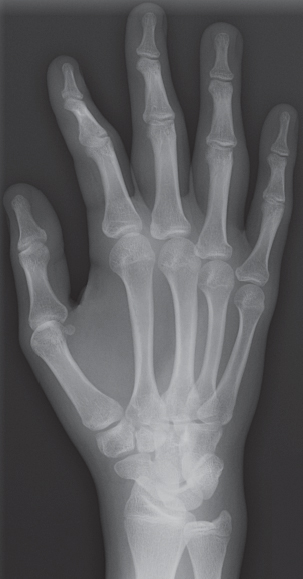

Bonelytics: Advanced Bone Age Assessment

Bonelytics is an advanced web-based platform that utilizes artificial intelligence to assess bone age from hand and wrist X-rays. Key features include:

• Automated bone age assessment using deep learning models